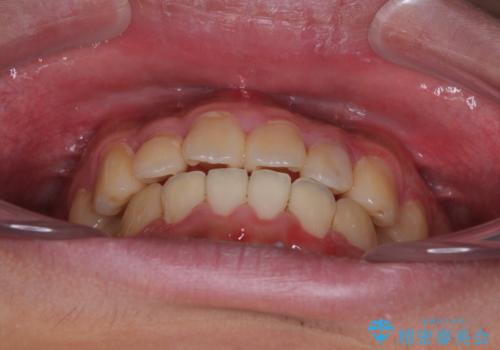

気になっていたクロスバイトは速やかに改善され、1年間で治療を終えることができました。

治療開始前は汚れが多く、全体的に歯肉が腫れていましたが、矯正治療を通して腫れも少しずつ改善されました。